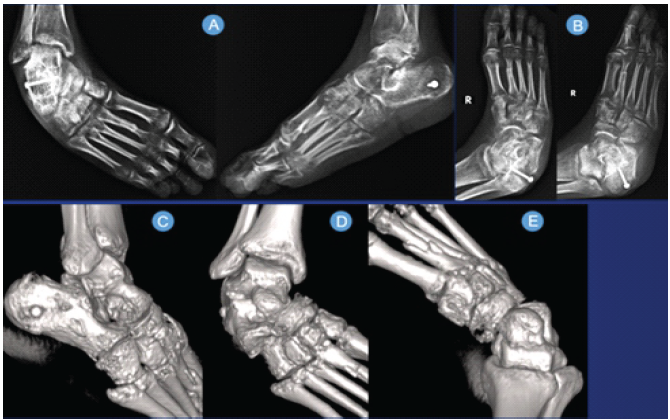

We present a case of a 24-year-old active Male, avidly participating in recreational activities before he suffered a road traffic accident causing a fall from his two-wheeler vehicle in February 2025. He sustained injuries to his right ankle. He was treated at a hospital near his home, where he was diagnosed a closed right extra-articular calcaneum fracture with second metatarsal shaft fracture, along with a deep abrasion over the dorsum of the ankle and foot. He was operated for the same with screw fixation of the calcaneum fracture with percutaneous pinning for the second metatarsal fracture (Fig. 1).

Figure 1: (A, B, C) Radiographs at the time of injury; (D, E, F) Three-dimensional computed tomography scans at the time of injury. (G, H) Post-operative radiographs after index surgery at the previous center.